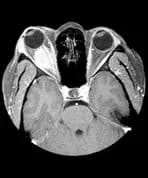

Right Orbital Mass

A patient presents with right-sided ocular pain and parietal headaches.

A large ovoid intraconal mass is shown in the right orbit. It does not extend intracranially or into the optic canal and it is transversed by the optic nerve. The appearances are most likely to be those of a glioma.